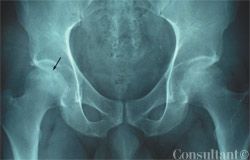

Photo Essay: Images of Hip Pain